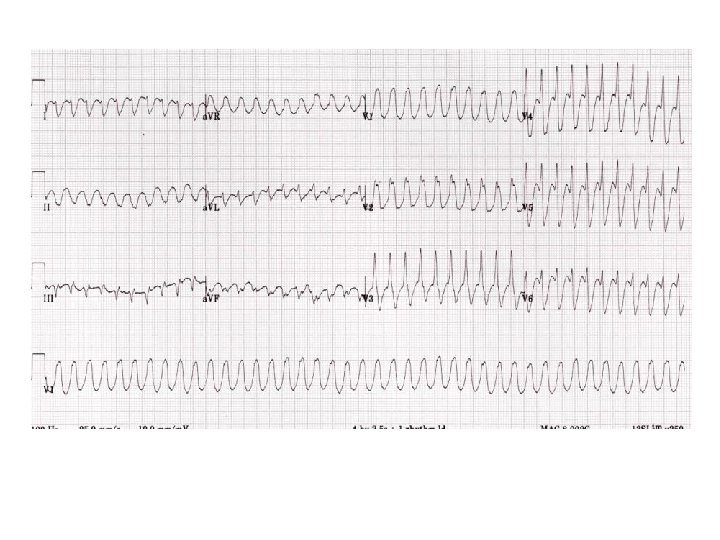

A 57 year old man has two hour history of palpitations. On examination he is sweaty and has a BP of 100/50 but denies chest pain or breathlessness. • Name two diagnoses which would explain this ECG picture? (2 marks) • He then drops his BP to 80/60. What treatment is required? (1 mark)